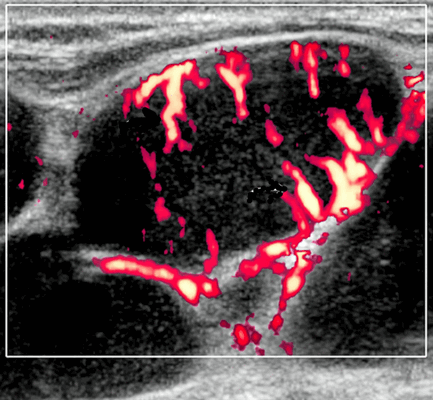

Допплерография может помочь в диагностике гепатокарциномы. Как упомянуто выше, ожидается, что трехмерное ультразвуковое допплеровское ультразвуковое моделирование восстановит сосудистую архитектуру опухолей печени, как показано селективной ангиографией. Между тем, цветное ультразвуковое допплерографическое картирование в большинстве гепатоцеллюлярных карцином показывает множественные цветные пятна, соответствующие срезам сосудов, и часто некоторые периферические сосуды (рисунок «корзина»): «поющая» опухоль с дуплексным ультразвуковым доплером или «светящаяся» опухоль с цветным картированием является признаком, указывающим на гепатокарциному.

Этот доплеровский паттерн, при подозрении на рак печени, очень отличается от одной гепатоцеллюлярной карциномы к другой: некоторые из них сильно васкуляризованы, другие намного меньше, что связано с наличием обильного жира или некроза. К сожалению, цветовые узоры при гепатокарциномах похожи на такие же проявления, связанные с другими типами опухолей, как злокачественных, так и доброкачественных. Дуплексное ультразвуковое доплеровское исследование может быть более конкретным, поскольку показано, что только гепатоцеллюлярные аденомы показывают сдвиги скорости выше 4 кГц, но такие пики скорости редки.

- Цветной допплер: смешанная васкуляризация с выраженным сосудистым рисунком и наличием периферической васкуляризации. Периферическая сосудистая сеть редко встречается в узлах НХЛ

Цветовой допплер: смешанная сосудистая сеть с выраженными внутриузловыми сосудами и наличием периферической сосудистой системы. Одна только периферическая сосудистая сеть редко встречается в узлах НХЛ. Спектральный допплер: переменное интранодальное внутрисосудистое сопротивление, которое носит неспецифический характер.